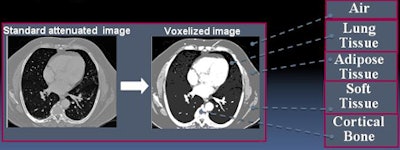

Image reconstruction of the full field-of-view was performed for the coronary arteries, pulmonary veins, or thoracic aorta with scan lengths ranging from 120 mm to 600 mm. The datasets were processed offline with a prototype Monte Carlo simulation tool (Philips) that enabled the adjustment of both tube potential and tube current-time product, utilized original scan parameters, and modeled scanner geometry including the tube start angle.

Each dataset was then "voxelized" to create a patient-specific virtual phantom. Each voxel was assigned a material type based on a priori global HU classification intervals per the International Commission on Radiation Units and Measurements Report 44.